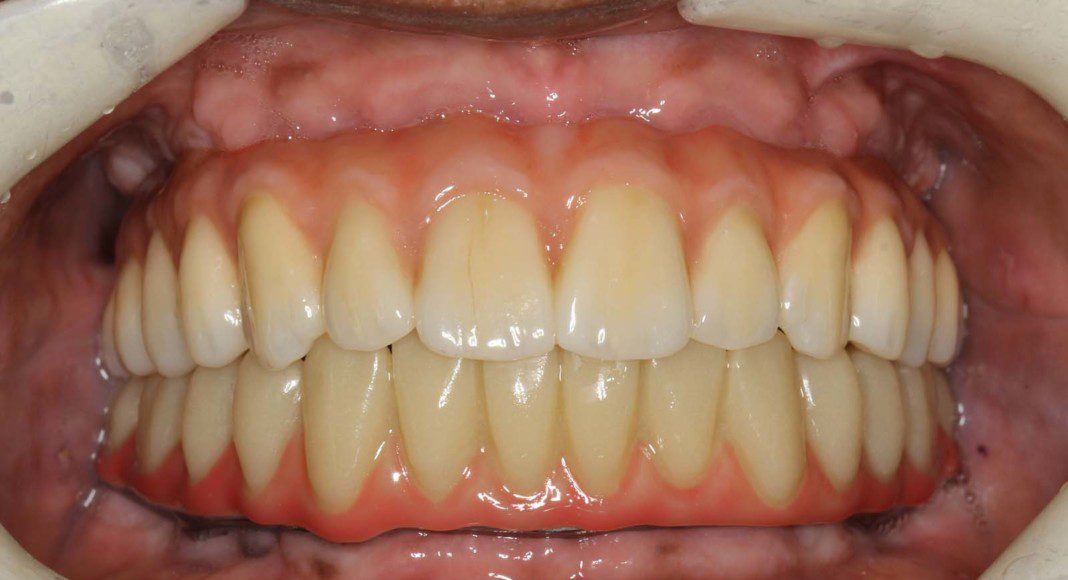

Upper and lower wax try-in. Here we test the aesthetics, tooth display and bite. If there is any compromise, concern, or large bite discrepancy, we make notes, take pictures and a new bite and schedule another try-in. We do as many try-ins as necessary to make sure everyone is happy. After the wax try-in is approved, nothing can be changed.

The most important view of the try-in is with the patient fully animated (full, unrestrained smile). This is how we reveal our teeth in social settings. Most patients have a controlled, comfortable smile at these try-ins. That is not enough… we must get the patient to loosen up and smile BIG!